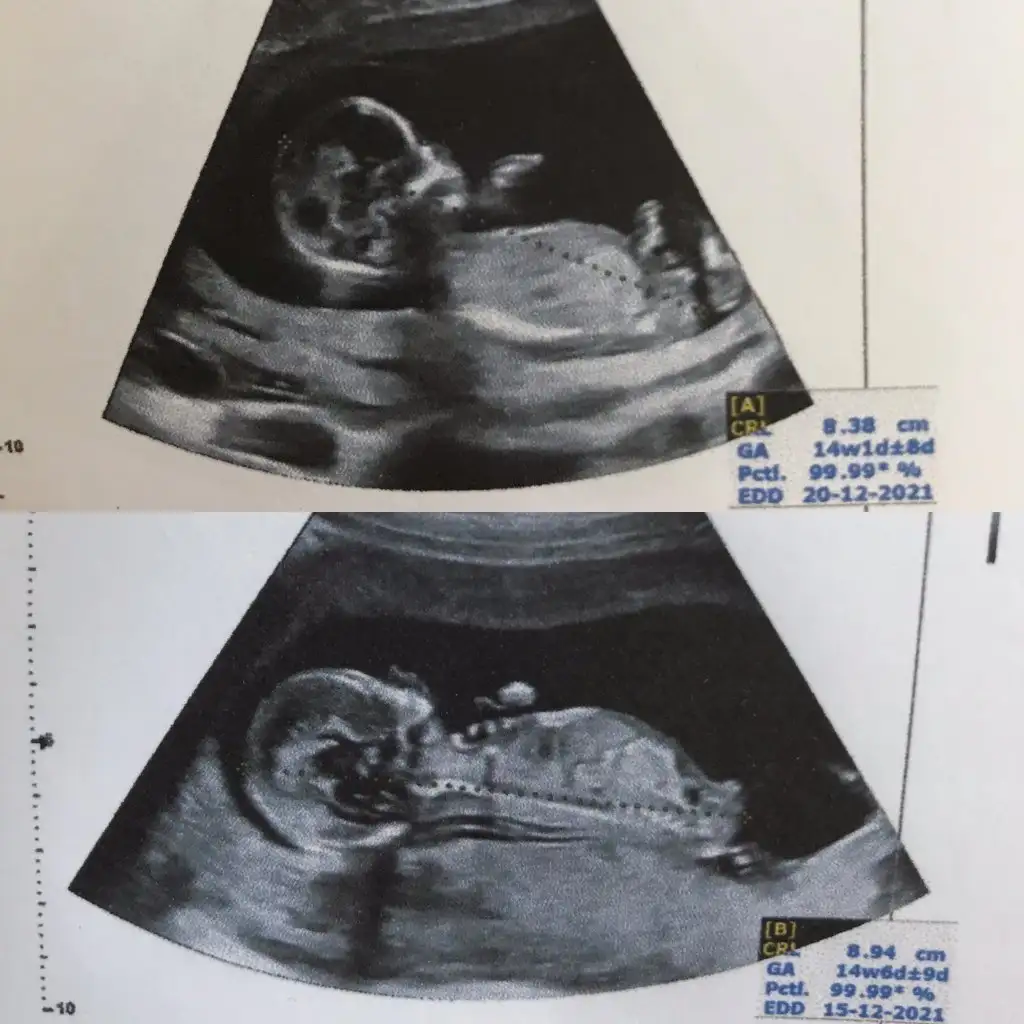

Benim ikiz bebeklerime de bir tahminde bulunurmusunuz

Eki Görüntüle 2889229 Eki Görüntüle 2889231

Haftası büyük olan erkek

haftasi küçük olan kız![]()